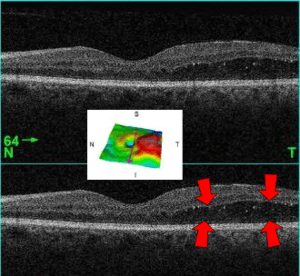

| A 61-year-old man with medical history of type 2 diabetes that presents a macular edema, evidenced by an OCT (the edema marked with arrows). The central image is a 3D reconstruction of the retinal thickness (the edema is coloured in red). | |

Macular edema occurs when fluid and protein deposits collect on or under the macula of the eye (a yellow central area of the retina) and causes it to thicken and swell (edema). The swelling may distort a person's central vision, because the macula holds tightly packed cones that provide sharp, clear, central vision to enable a person to see detail, form, and color that is directly in the centre of the field of view.